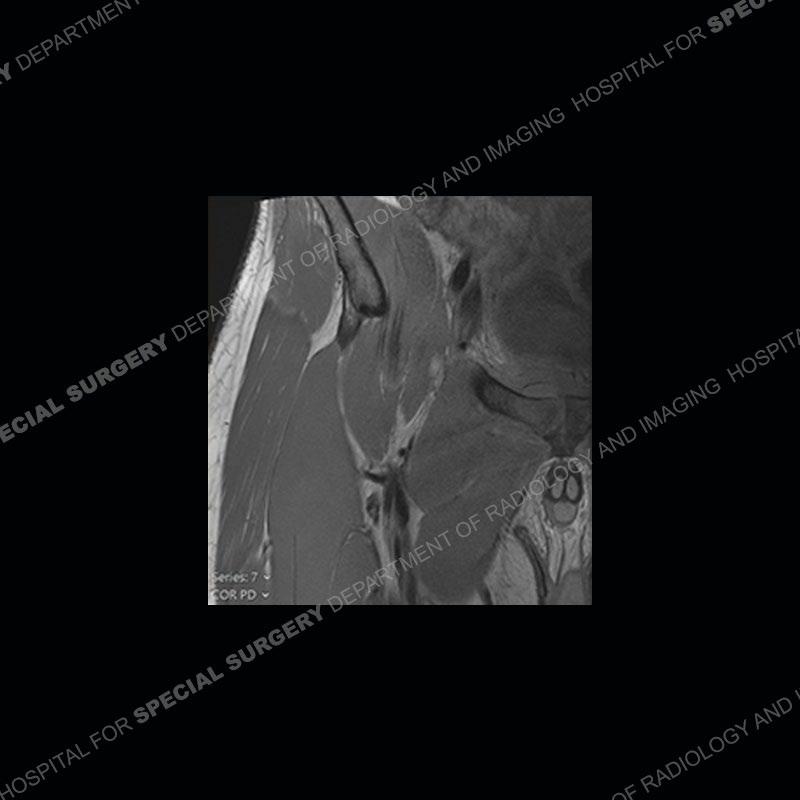

Radiographs did not demonstrate any clear abnormality. The MRI shows markedly abnormal signal of the right superior pubic ramus and abnormal signal/”mass” extending into the adjacent soft tissue. The inferior articular surface of the ramus showed what was thought to be bony destruction. CT examination shows a destructive process of the right superior pubic ramus.

Subsequent MRI in a very short time interval shows markedly increased abnormality of the ramus and increased edema and “mass” of the soft tissue. Post contrast imaging shows multiple, rim enhancing collections of the soft tissue and similar albeit less conspicuous enhancing collection of the ramus.

Diagnosis: Osteomyelitis and Soft Tissue Abscess